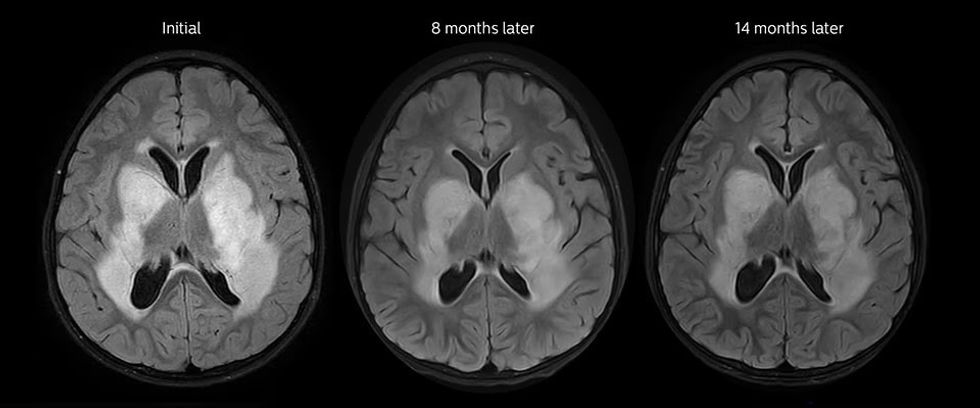

Tumoret e trurit diagnostikohen më së miri me CT dhe MRT me kontrast.